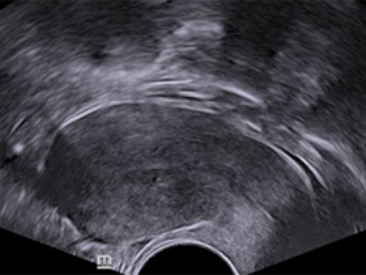

Obrazy kliniczne